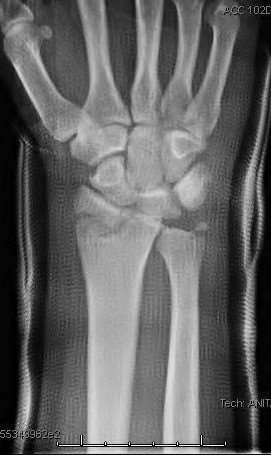

A 35-year-old woman reports wrist pain after a fall onto an outstretched hand. On exam, she has focal tenderness over the wrist snuffbox. A radiograph and CT image are shown in Figures A and B. What is the proper treatment of her injury?